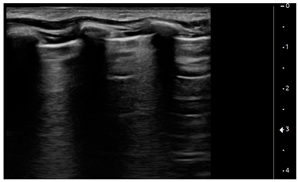

We used the following definitions to characterize the LUS patterns [15]:

- A-lines: normal appearance of horizontal, equidistant, parallel artefacts originating at regular intervals from the pleural line (visceral and parietal pleura)

- B-lines: laser-like signals arising from the hyper-echoic pleural line, extending to the bottom of the screen without fading and moving synchronously with respiration

- Subpleural consolidation: Small, triangular, or oval shaped, echo-poor region adjacent to the pleura without a tissue-like pattern (AB)

- Lobar consolidation: Large, hypoechogenic region adjacent to the pleura with a tissue-like pattern (AB) and an irregular pleural border

- Pleural effusion: Anechoic or hypoechoic collection external to lung parenchyma, typically in a dependent lung region with or without respiratory movement of the lung within the effusion (flapping lung)

Using the mentioned LUS semeiotics, lung aeration and lung pattern were classified following a 5 point score:

- Normal lung sliding, regular pleural line, and A lines

- Vertical artifacts, pleural line indented with several B-lines per field in the posterior regions

- Vertical artifacts, pleural line indented with several B-lines per field in all regions

- Broken pleural line with subpleural consolidations < 1 cm

- Consolidations > 1 cm with or without pleural effusion (Table 1).